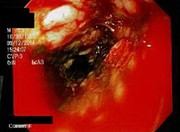

Esophageal Dieulafoy's lesion: an exceedingly rare cause of massive upper GI bleeding

George P. Malliaras and others

Journal of Surgical Case Reports, Volume 2016, Issue 6, June 2016, rjw074, https://doi.org/10.1093/jscr/rjw074